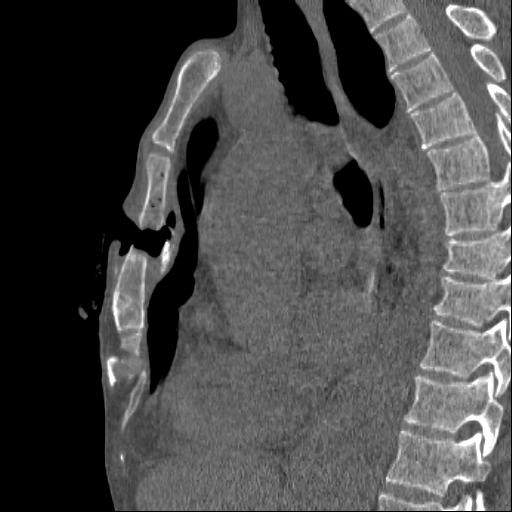

Повреждение грудины, КТ.

После автомобильной травмы с повреждением грудины через пару недель усиливаются боли, температура...